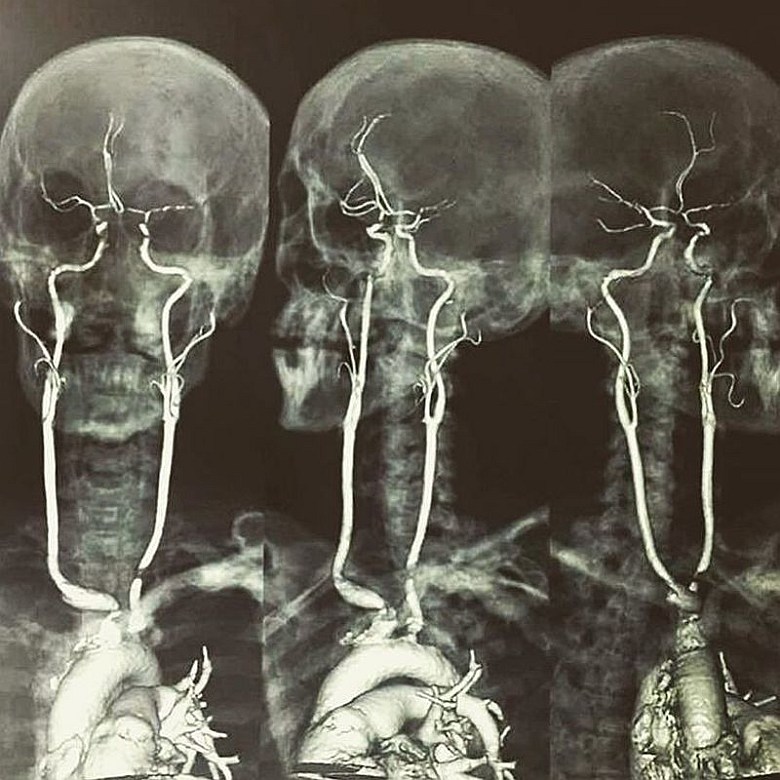

Tętnice szyjne na skanie rezonansu magnetycznego (MRI)